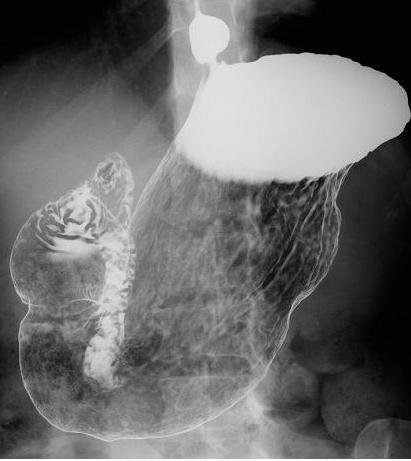

一般的によく知られているものでは、検診などで行われる胃の造影検査(バリウム検査)があります。